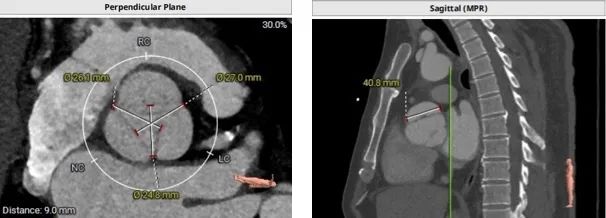

术前超声显示主动脉瓣大量反流:

猪尾放置于无冠窦行根部造影:

定位件于瓣环下打开,将瓣膜件降至合适平面,造影确认:

定位件入窦,造影:

调整导丝,使得瓣膜同轴:

再次造影确定位置:

释放瓣膜,复查根部造影,未见明显反流,瓣膜形态和位置满意,双侧冠脉未见遮挡征象:

退出介入器:

血管减影造影,瓣膜形态正常、未见瓣周漏:

即刻复查食道超声,长轴切面显示瓣架深度合适,瓣叶启闭正常,未见明显瓣周漏: